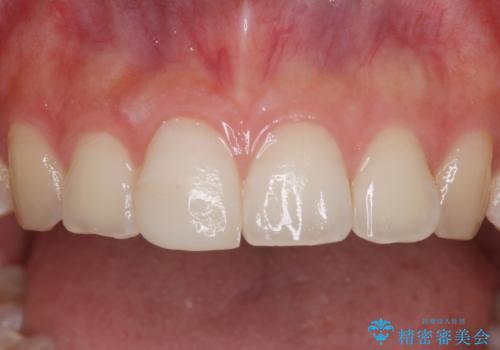

転んで前歯の先端1/3ほどが欠けており、近医にて応急処置としてコンポジットレジン修復がされていました。

審美性や舌触り、今後の歯への負担などを考え、オールセラミッククラウンにて補綴治療を行うこととしました。